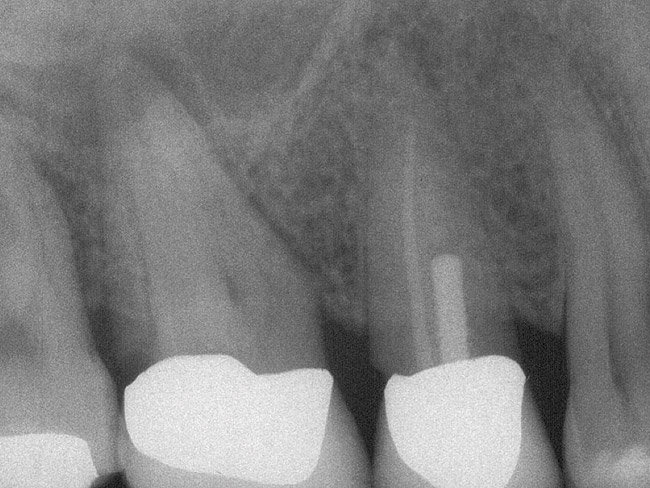

Figure 5a  Tooth No. 30 The preoperative radiograph revealed a periapical radiolucency and transported canals in the mesial root.

Figure 5a

Figure 5b  This procedural error may have delayed the progress of therapy or even made it impossible to thoroughly clean and shape the canal terminus. Root-end surgery was performed to enucleate the periapical pathology and debride previously uncleaned parts of the canals. On the apically resected root surface, an uncleaned portion of 1 canal and an isthmus connecting the 2 main canals became visible under high magnification (Figure 5B), which were prepared to 1 retrocavity using ultrasonic tips (Figure 5C) and filled with MTA (Figure 5D).

Figure 5b